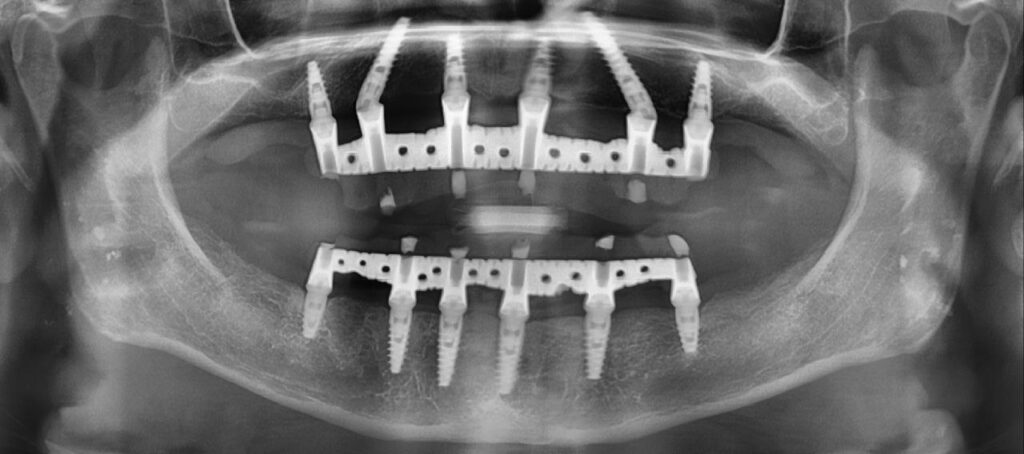

La tomografia 3D ci consente di pianificare ogni intervento con massima precisione e sicurezza.